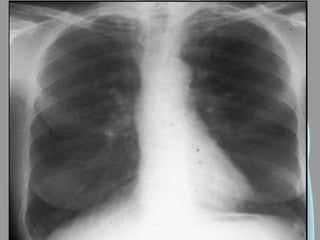

Derrame Pleural

• Hipotransparência;

• Denso e homogêneo;

• Em PA quando possuir

mais de 300ml;

• Em Laurell em

quantidades <300ml;

• Desvio do mediastino

para o lado oposto;

• Velamento do seio

costofrênico.

Derrame Pleural • Hipotransparência; •Denso e homogêneo; • Em PA quando possuir mais de 300ml; • Em Laurell em quantidades <300ml; • Desvio do mediastino para o lado oposto; • Velamento do seio costofrênico.